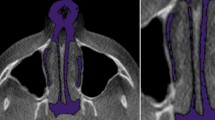

In Dolphin 3D, the scans were uploaded and re-oriented to a modified Frankfort horizontal (FH) axial plane determined by three landmarks: right porion, right orbitale, and left orbitale and checked in three views similar to previous reports [7]. On the right sagittal view, the horizontal reference line passed through porion and the right orbitale. On the frontal view, the horizontal reference line passed through the right and left orbitale, and the vertical reference line passed though Nasion (N) and the anterior nasal spine (ANS) perpendicular to the horizontal reference line. On the transverse view with the nose pointing downwards, the vertical reference line passed through crista galli and basion (BA) (Fig. 1).

Dolphin 3D skull orientation, right sagittal view (left), frontal view (middle), and transverse view (right). Images rendered using Dolphin (http://dolphinimaging.com)

Once the scans were re-oriented, the airway was defined. The airway was assessed from the root of the clivus superiorly to the base of the epiglottis inferiorly, and from PNS anteriorly to the pharyngeal wall posteriorly and laterally. The airway was divided into three subregions: nasopharynx (NP), oropharynx (OP), and hypopharynx (HP). Table 2 and Fig. 2 show the technical limits for each subregion adopted from the limits proposed by Guijarro-Martinez and Swennen [7]. The root of clivus was identified by the ventral end of the spheno-occipital synchondrosis. In younger subjects, when there was a gap at clivus, the lower margin of this gap was chosen.

Dolphin 3D technical limits of the nasopharyngeal (left), oropharyngeal (middle), and hypopharyngeal (right) airway subregions used during three-dimensional airway analysis. Images rendered using Dolphin (http://dolphinimaging.com)